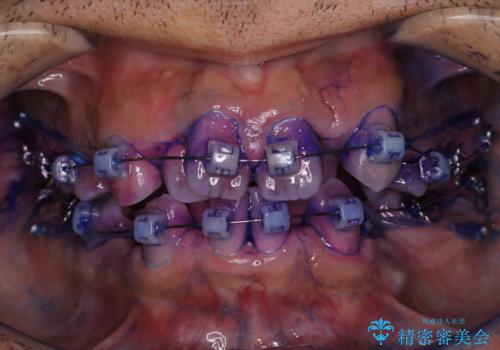

表のワイヤー装置で矯正中にPMTCで綺麗にお掃除

担当医 歯科衛生士